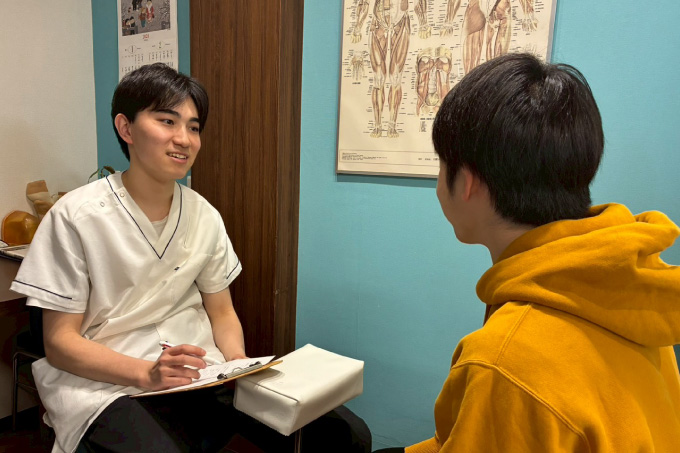

丁寧な問診と説明で、不安を安心に変える対応力

当院が大切にしているのは、施術前のカウンセリングです。

患者さまの主訴を丁寧に傾聴し、不安や疑問をしっかり受け止めたうえで、痛みの原因や施術方針を分かりやすくご説明します。

さらに、施術だけでなく、ストレッチ指導や筋力強化、生活習慣の見直しなど、日常生活でできる改善策もご提案。

お一人おひとりに合わせた施術プログラムで、症状改善と生活の質の向上を目指します。

1問診

問診表にご記入ください。

2検査

診察スペースにて問診・触診をします。

3施術方針の説明

痛みの原因となっている場所、施術内容について説明します。